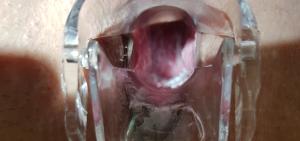

Вагинальный мазок - это диагностический метод, часто используемый в гинекологии и венерологии.

Мазок из влагалища является важным анализом, который свидетельствует о состоянии здоровья половых органов женщины.

Вагинальный мазок на флору берут при визите женщины к гинекологу или венерологу.

Исследование вагинальных мазков проводится обязательно при наличии жалоб на зуд, жжение или наличие выделений.